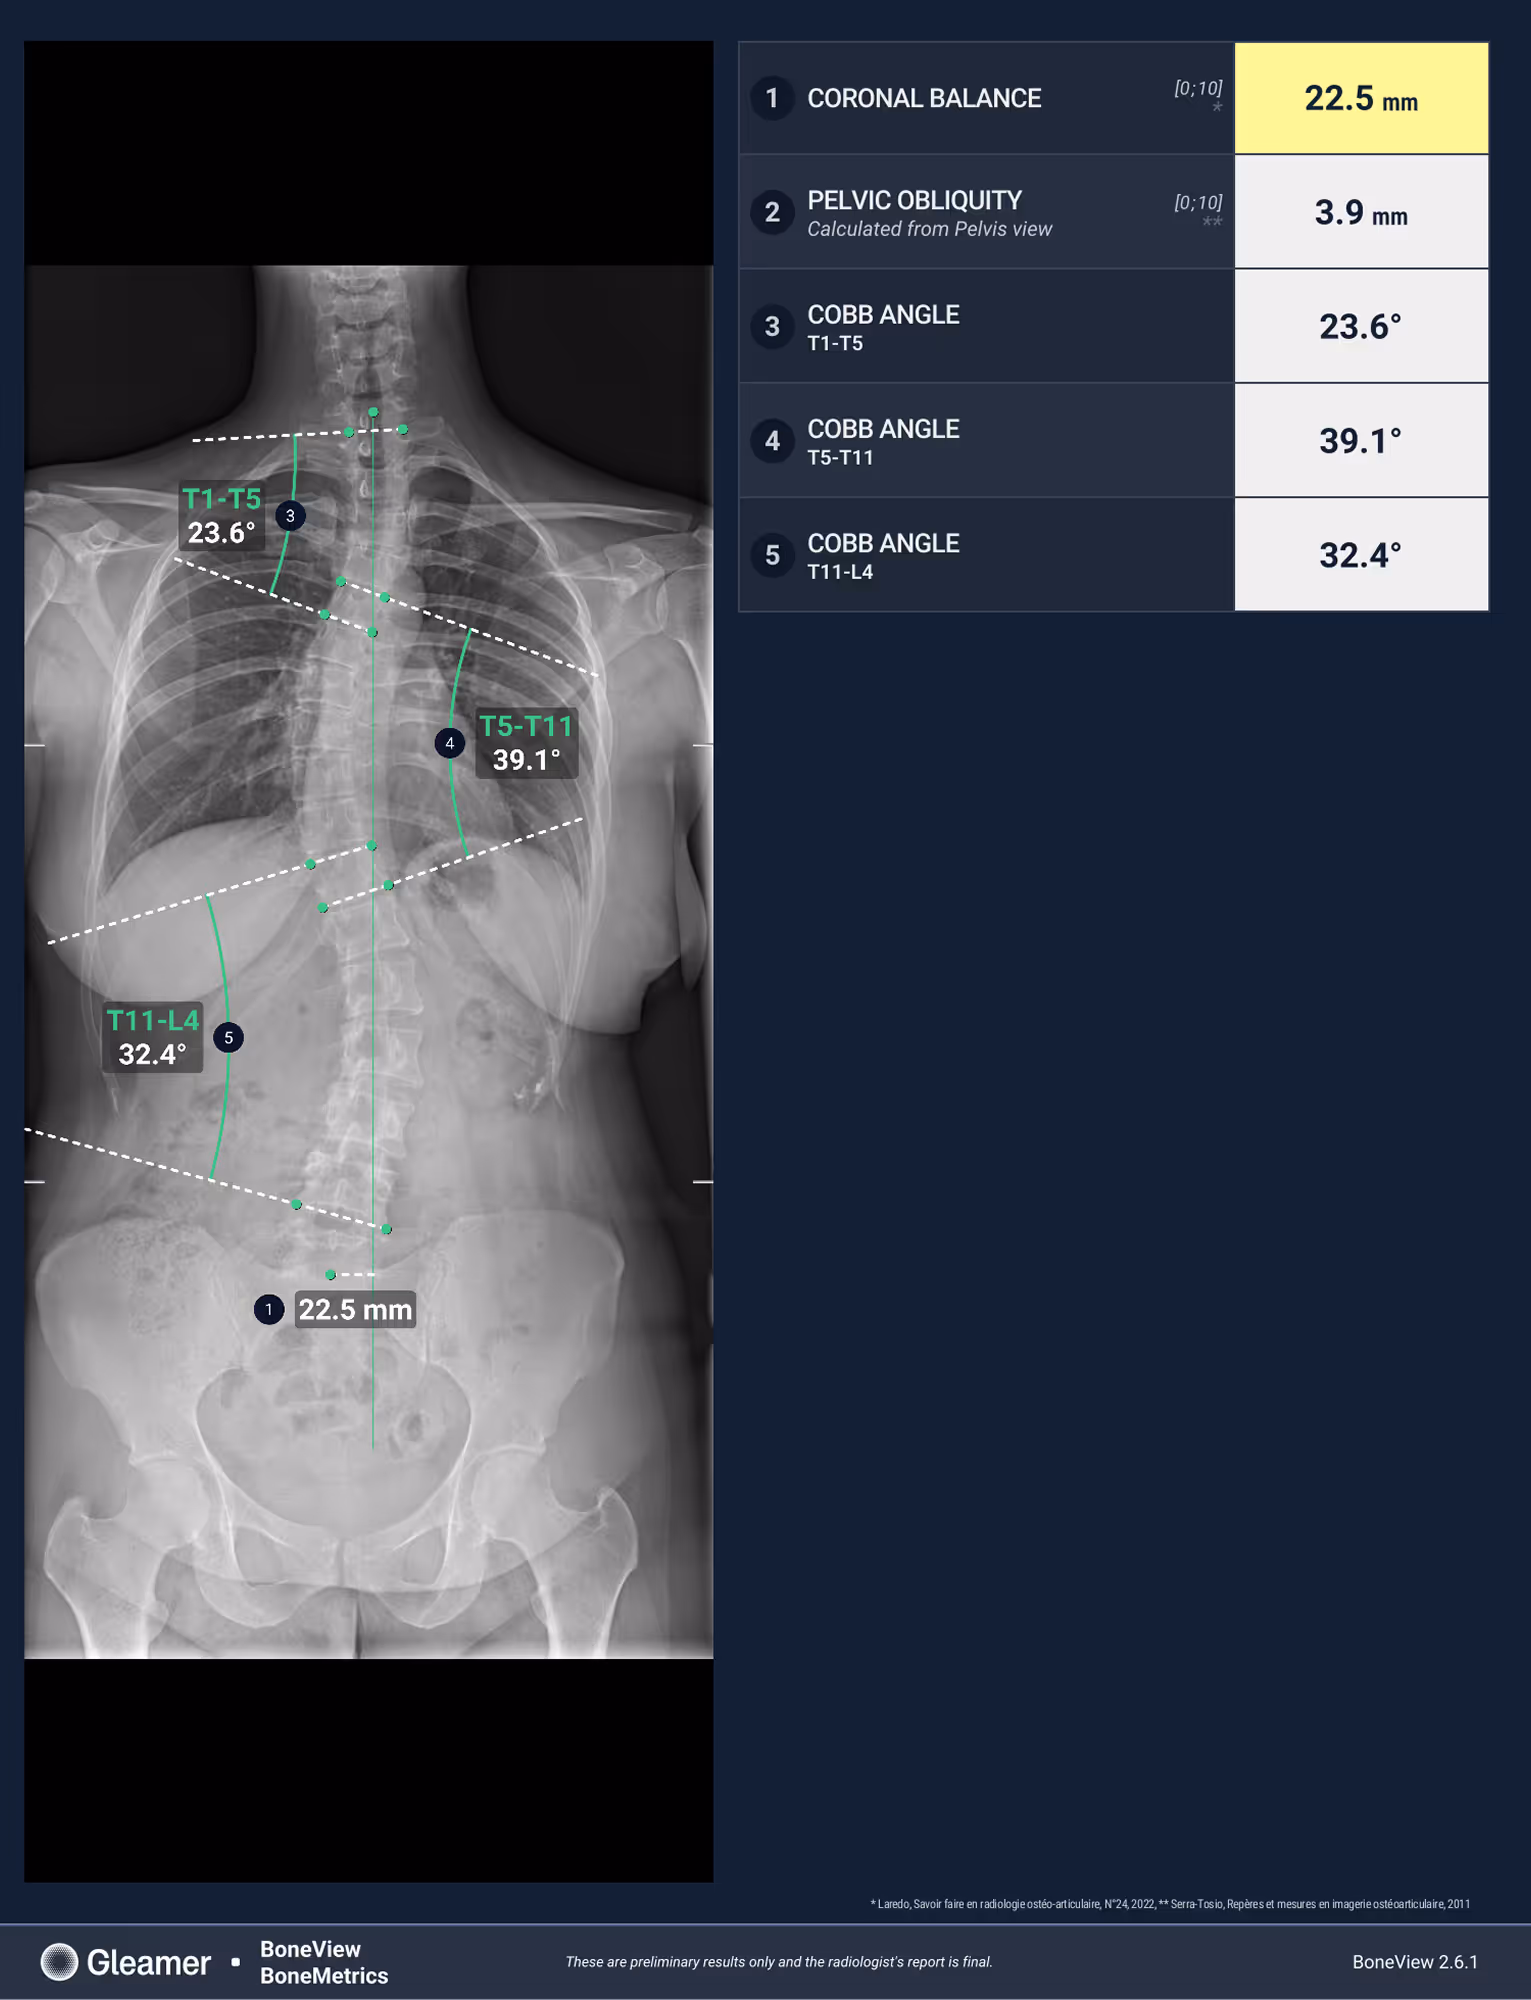

Indication

A 30-year-old female presenting with dorsal main, and a history of untreated scoliosis in childhood.

Results

BoneMetrics identified three distinct Cobb angles, consistent with a triple curve scoliosis.

Frontal

Cobb angle

Pelvic obliquity

Coronal balance

Risser index